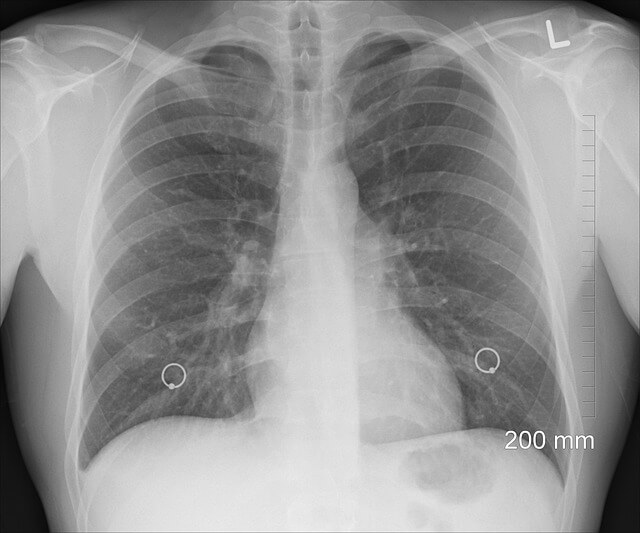

폐에 물이 차는 증상

폐에 물이 차는 것은 폐부종 또는 흉막삼출이라는 상태를 의미할 수 있으며, 여러 가지 원인에 의해 발생합니다. 대표적인 증상은 다음과 같습니다.

- 호흡곤란: 가벼운 활동만으로도 숨이 차며 심한 경우에는 가만히 있어도 숨쉬기 어렵습니다.

- 기침: 마른 기침이 계속되거나 거품이 섞인 가래가 나올 수 있습니다.

- 가슴 통증: 흉막삼출의 경우 가슴 부위의 불편감이나 통증을 유발할 수 있습니다.

- 청색증: 산소 공급이 부족하여 입술이나 손끝이 파랗게 변하는 증상이 나타날 수 있습니다.